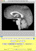

- Once the file is loaded, the image should appear in the display region. Tracer will

automatically take you to a plane in the middle of the image and will adjust the intensity of the

display to a (usually) reasonable value. If the display appears black, this may be a problem with

the automatic intensity adjustment, and you may need to set the intensity manually.